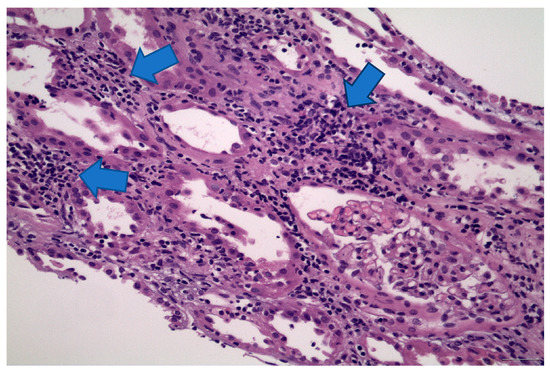

5. Case 4 Description: Pembrolizumab-Axitinib-Induced MCD

6. Discussion